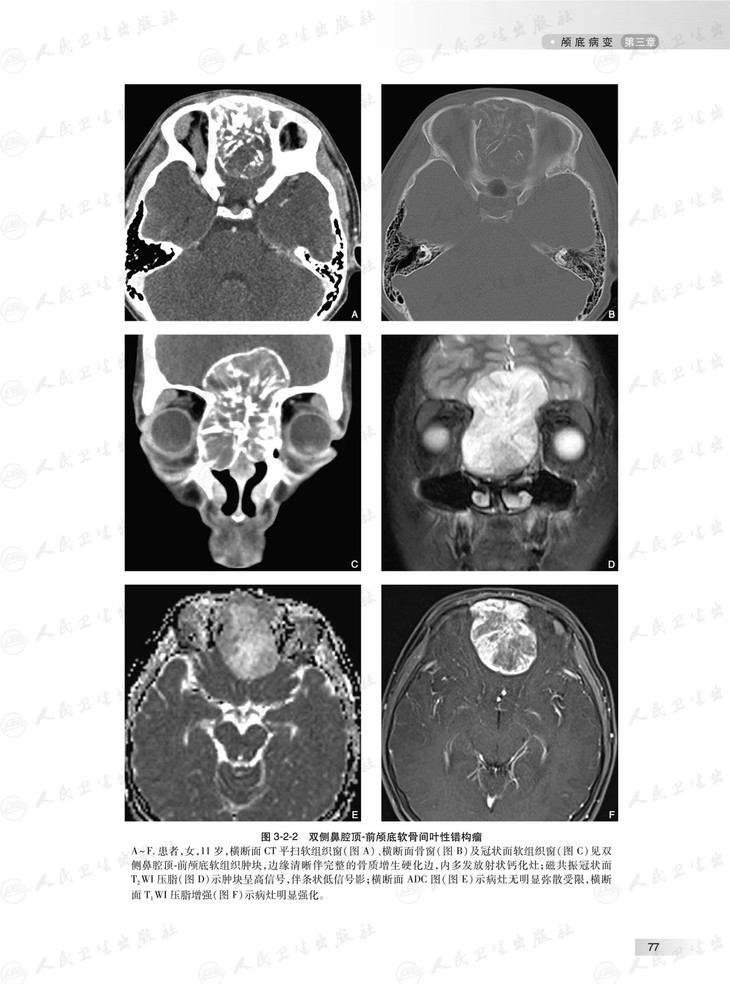

本书根据头颈部影像临床工作场景,对头颈部影像学征象或表现进行系统讲解和分析,头颈部包括的部位多,结构复杂细微,病变种类繁杂,每个部位的影像学征象和表现各有特点,据此,本书按照颅底、耳部、鼻腔与鼻窦、眼球与眼眶、咽喉部、口腔、颌面部、舌骨上颈部间隙和舌骨下颈部间隙等部位各成一章。头颈部外伤性病变有其自身特点,故独立成章。本书图文并茂,具有全面、系统、简洁和清楚的特点。